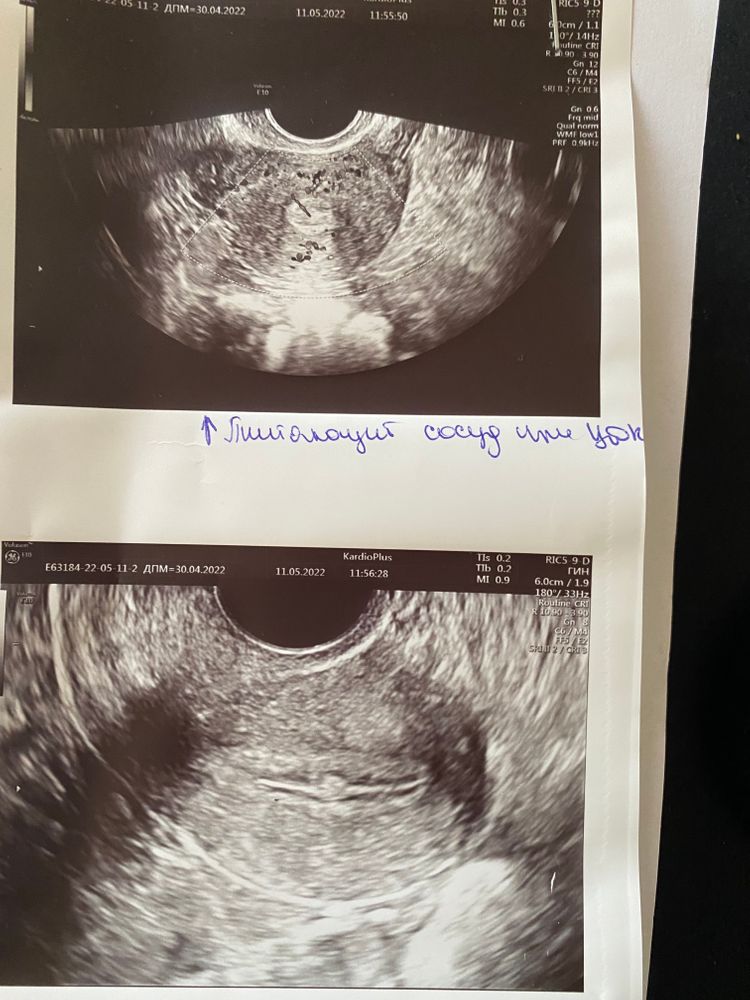

Akhmadalieva, да вот кто его знает. Но врач, которая нашла полип, говорила «вот точно он, вот питающий сосуд» и т.д и т.п. А врач, который как бы наоборот заинтересован в том, чтобы мне гистеру сделать, сказал, что полипа нет, говорит «могу тебе его нарисовать конечно, но пока вообще нет причин делать наркоз и все вмешательства»